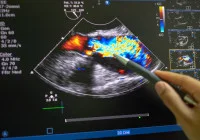

Accurate grading of hepatic steatosis is essential for effective management and intervention. While liver biopsy remains the diagnostic gold standard, its invasive nature limits broad applicability. Consequently, non-invasive imaging modalities—particularly magnetic resonance imaging proton density fat fraction (MRI-PDFF), controlled attenuation parameter (CAP) and attenuation coefficient (AC)—have been extensively studied as alternatives. A recent meta-analysis consolidates data from 38 studies, involving over 5000 patients, to assess the performance of these techniques against biopsy-verified diagnoses.

The study assessed the diagnostic accuracy of MRI-PDFF, CAP and AC across various steatosis grades—mild (≥S1), moderate (≥S2) and severe (≥S3). MRI-PDFF showed the highest diagnostic performance, with area under the curve (AUC) values of 0.99 for ≥S1, 0.89 for ≥S2 and 0.90 for ≥S3. CAP demonstrated slightly lower performance, particularly in diagnosing moderate and severe steatosis, with AUCs of 0.95, 0.84 and 0.77 for ≥S1, ≥S2 and ≥S3, respectively. AC provided competitive results, showing AUCs of 0.97, 0.90 and 0.89 for the respective grades.

Pooled sensitivity and specificity analyses revealed similar patterns. MRI-PDFF maintained high sensitivity and specificity, particularly for ≥S1 (95% and 98%, respectively). CAP achieved good sensitivity for all grades but lagged in specificity for ≥S2 (70%) and ≥S3 (65%). AC consistently delivered strong sensitivity and specificity across all grades, indicating its potential reliability.

Comparative analysis revealed that CAP underperformed in detecting ≥S2 and ≥S3 when compared to MRI-PDFF and AC, with statistically significant differences. This discrepancy highlights the limitation of CAP in stratifying steatosis severity, particularly in clinical populations where higher grades are more prevalent.